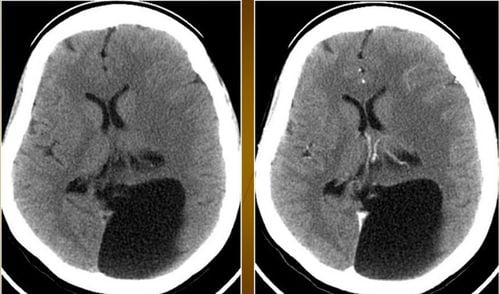

U nang màng nhện là nang nước trong não hoặc tuỷ sống chứa dịch não tuỷ, có rất ít sự thông thương với khoang dưới nhện. Nang này thường có nguồn gốc bẩm sinh xuất phát từ quá trình phân tách màng nhện khi còn là bào thai, thường là dạng tổn thương lành tính. Vậy bệnh u nang màng nhện liệu có nguy hiểm?